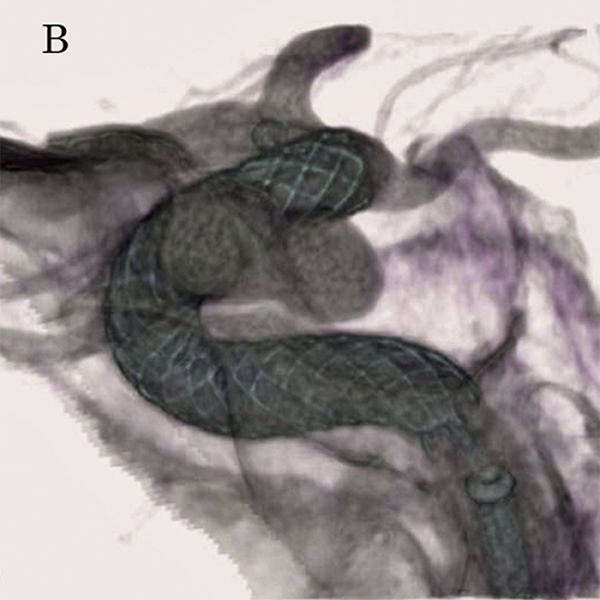

Малюнок 4: Симуляція CAA розміщення перемикача потоку (FD) (червоний: аневризма, синій: FD).

Малюнок 5B: Бічне флюороскопічне зображення, отримане за допомогою HD-детектора (3 дюйми) під час розміщення FD.